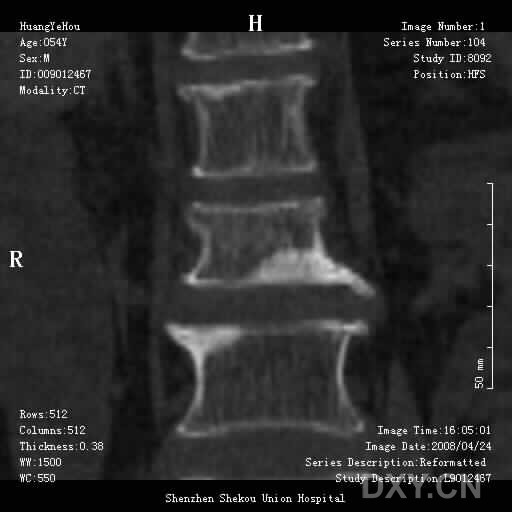

男,54岁,腰部外伤疼痛2小时!

1、腰3椎体压缩骨折

2、腰椎退行性变。

1.腰椎椎体压缩性骨折,  2. 退行性改变(局限性骨质密度增高.

前缘变窄;压缩骨折;椎体硬化征;退行性变